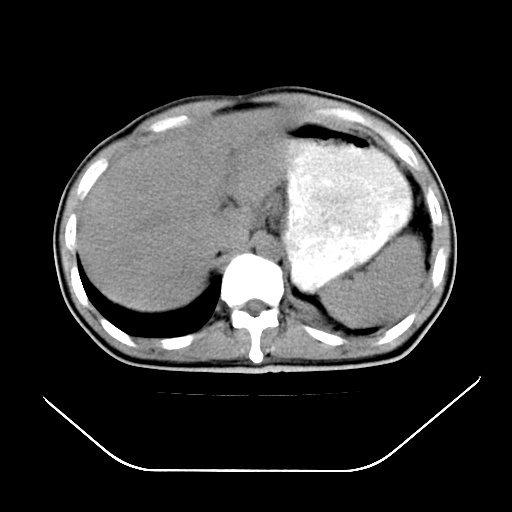

以下是引用深泽交通医院在2008-7-17 12:05:00的发言:[br]肝门淋巴结肿大;胆结石

以下是引用文莱在2008-7-17 16:32:00的发言:[br]胆囊结石 余未见异常

以下是引用随光逐影在2008-7-17 17:52:00的发言:[br]1)胆囊结石。2)肝门及胰头区淋巴结肿大可能(原因不明);建议行进一步检查。

以下是引用卜一在2008-7-17 16:37:00的发言:[br]支持胆囊结石!!!至于胰头区病变——建议强化后再定论!